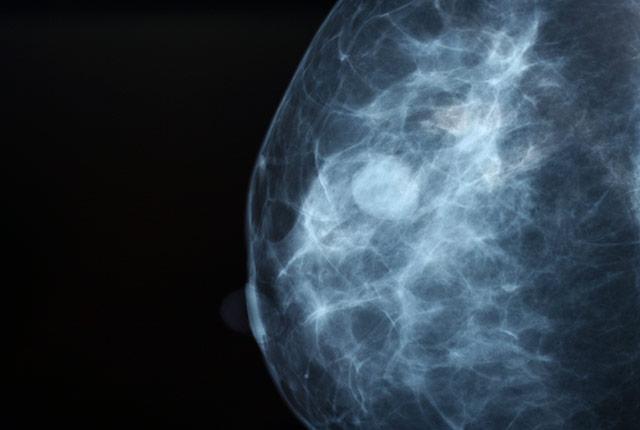

Machine-learning algorithms could help improve the accuracy of breast cancer screenings when used in combination with assessments from radiologists, according to a study published today in JAMA Network Open.

Mammography screening is commonly used for early detection of breast cancer. While this detection tool has generally been effective, mammograms must be assessed and interpreted by a radiologist, using human visual perception to identify signs of cancer. This has led to false-positive results in an estimated 10 percent of the 40 million women who receive routine annual breast cancer screenings in the United States.

The findings showed that, while no single algorithm outperformed radiologists, a combination of methods in addition to radiologists' assessments improved screenings' overall accuracy. The research was conducted by IBM Research, Sage Bionetworks, Kaiser Permanente Washington Health Research Institute, and the UW School of Medicine. It involved hundreds of thousands of de-identified mammograms and clinical data from Kaiser Permanente Washington and the Karolinska Institute in Sweden.